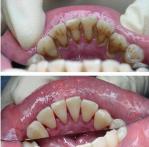

In the early stage of gingivitis, bacteria in plaque build up, causing the gums to become inflamed and to easily bleed during tooth brushing. Although the gums may be irritated, the teeth are still firmly planted in their sockets. No irreversible bone or other tissue damage has occurred at this stage.

When gingivitis is left untreated, it can advance to periodontitis. In a person with periodontitis, the inner layer of the gum and bone pull away from the teeth and form pockets. These small spaces between teeth and gums collect debris and can become infected. The body’s immune system fights the bacteria as the plaque spreads and grows below the gum line